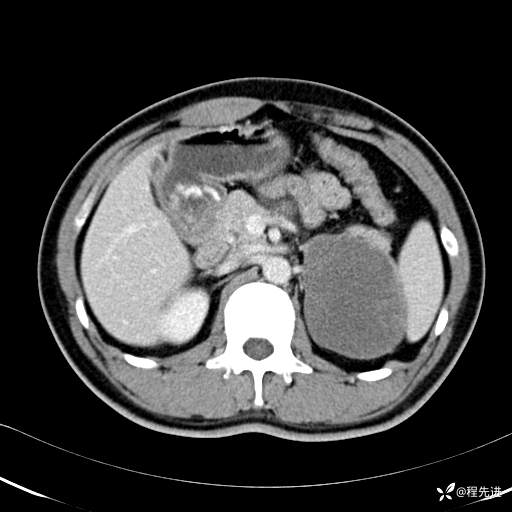

动脉期: